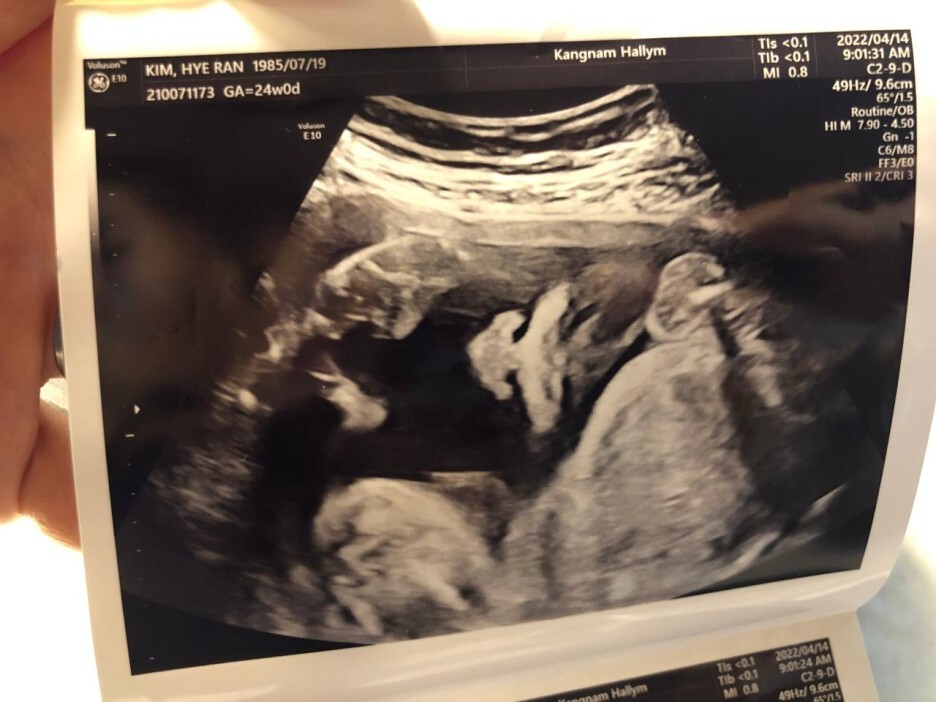

4월 14일 목요일(24주차 0일)

BPD(Biparietal Diameter, 위에서 볼 때 태아 머리 단면의 가장 긴 길이): 5.59cm

HC(Head Circumference, 태아 머리둘레): 21.64cm

AC(Abdominal Circumference, 배 둘레): 19.99cm

EDD(Expected Date of Delivery, 출산 예정일): 2022년 8월 4일

FL(Femur Length, 허벅지뼈 길이): 4.32cm

GA(Gestational Age, 임신 주차): 24주차 1일

EFW(Estimated Fatal Weight, 태아 예상 체중)=EBW(Estimated Body Weight): 680g

FHR(Fetal Heart Rate, 심장박동 수): 155bpm

CL(Cervical Length, 자궁경부 길이): 3.77cm

AF(Amniotic Fluid, 양수): 정상